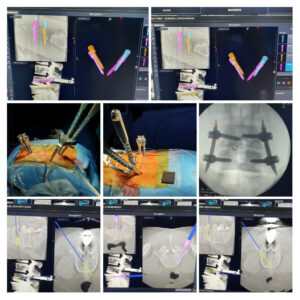

Minimally invasive stabilization of Burst fracture in spine .